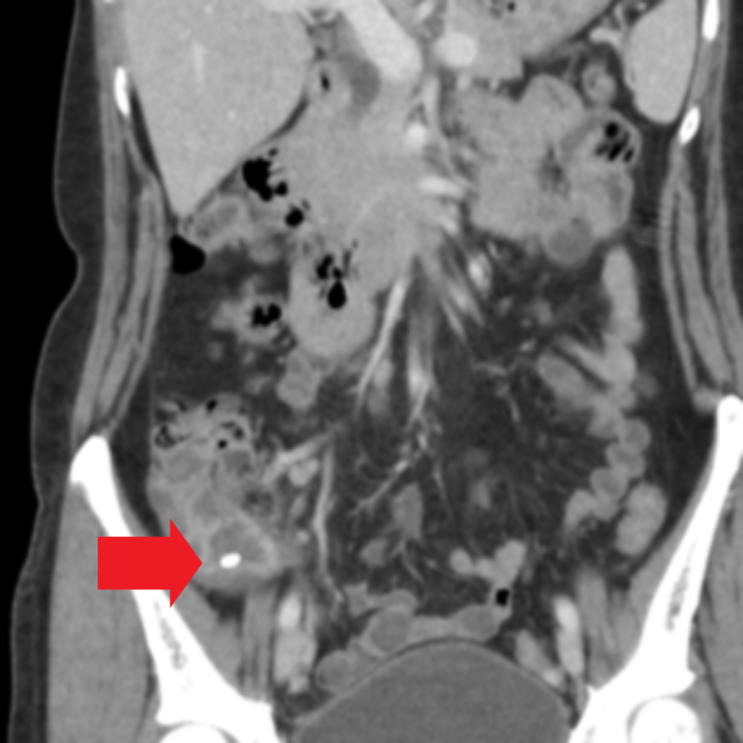

복부CT 사진을 보면 충수결석을 동반한 충수돌기 벽의 전반적 비후를 확인할 수 있습니다. 급성 충수돌기염(맹장염) 진단하여 추가 수술적 치료 위하여 상급병원 전원하였습니다.

• 복부CT: 충수결석을 동반한 충수돌기 벽 비후 (화살표 표시) 복부CT: 충수결석을 동반한 충수돌기 벽 비후 (화살표 표시)